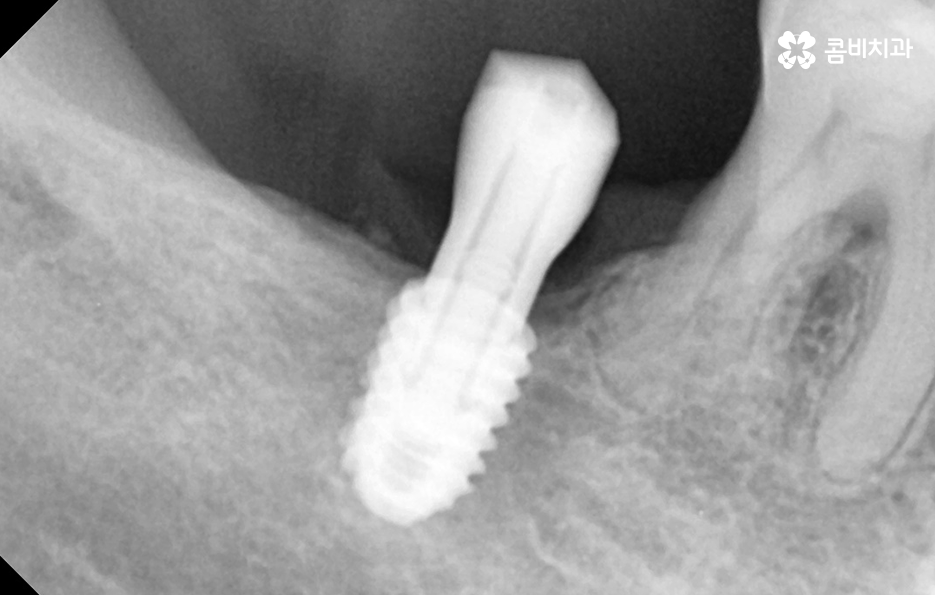

임플란트의 시술 원리는 잇몸 뼈에 식립하게 되기 때문에 충분한 골조직이 없을 때는 시술 성공률도 낮아질 뿐 아니라 장기적인 안정성도 떨어지기 때문에 잇몸 뼈가 부족하신 분들은 뼈이식을 추가적으로 해야할 수 있어요

만약 치주염으로 인해 50대임플란트 해야 하는 분들의 경우에는 뼈이식을 추가적으로 받아야 하는 경우가 있겠고 임플란트의 안정성을 확보하기 위해서는 임플란트를 고정해줄 수 있는 일정한 두께와 식립 깊이, 골질이 건강해야 하는데요

또한 뼈이식을 해야 하더라도 잇몸을 되도록 보존하는 치료를 하고 치료 시점을 의사와 잘 상의한다면 뼈이식의 양을 줄일 수 있고 회복기간도 상대적으로 줄일 수 있다는 점에서 임플란트 치료 원리를 먼저 이해하시고 대처하시길 바라고 있어요